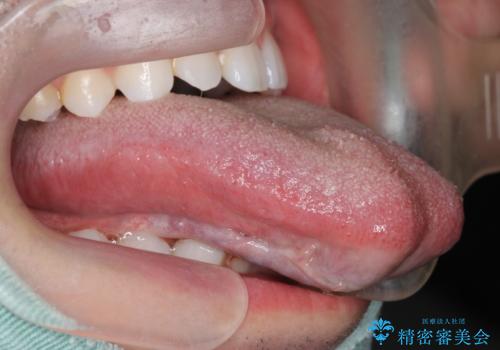

切除後、しっかり上にもつくようになり、前にも大きく出せるようになりました。

発音については、大人よりも子供の方が効果が期待できますが、舌の可動域が増えるため、おすすめです。た行、ら行などは、舌を上につけないと舌足らずになってしまします。